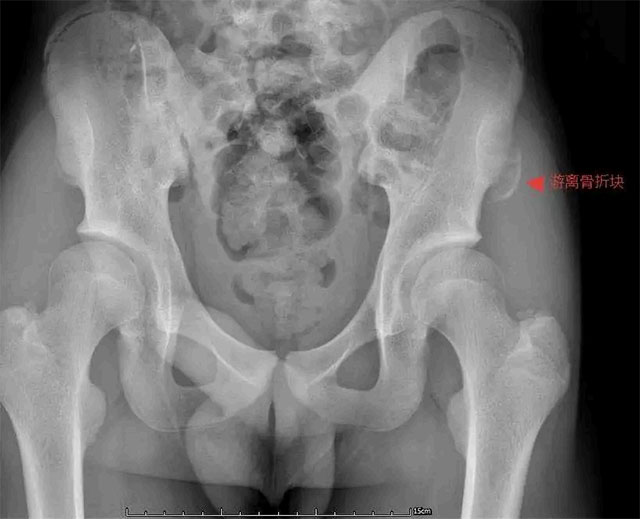

14岁的短跑主力小张,在校运会起跑训练中猛地蹬地发力,左髋部瞬间传来“撕裂般”剧痛,当场瘫坐跑道,冷汗浸透运动服。检查显示,他的左髂前上棘撕脱骨折,骨折块移位达3cm,正是起跑时肌肉的猛烈收缩牵拉导致了损伤。

16岁足球前锋小郑在友谊赛冲刺射门时,右脚发力的刹那右侧髋部钻心疼痛,无法站立,确诊骨折移位2.5cm,不得不暂别绿茵场。

15岁的小王在800米测试后半程突发左髋痛,步伐错乱,勉强冲过终点后弯腰、转身都困难,就医后发现骨折块移位2.2cm,一次常规测试竟引发骨折让他始料未及。

针对青少年生理特点与运动需求,科室制定个性化治疗方案。对于骨折移位超1cm、关节功能受限或运动需求高的患者,优先采用微创切开复位内固定术——仅2-3cm的微创切口,沿髂嵴精准切开避开神经,最大程度减少组织损伤,再根据骨折情况用空心螺钉等方式坚强固定。